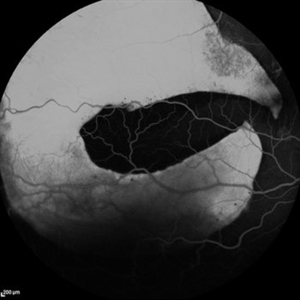

Giant RPE-Rip

Sep 5 2021 by Hemanth Murthy, MBBS, MD, FASRS

Fundus fluorescein angiography of a 50 year-old patient with spontaneous giant RPE rip.

Photographer: Mr Veda Vyas

Imaging device: Heidelberg HRA

Condition/keywords: RPE-Rip